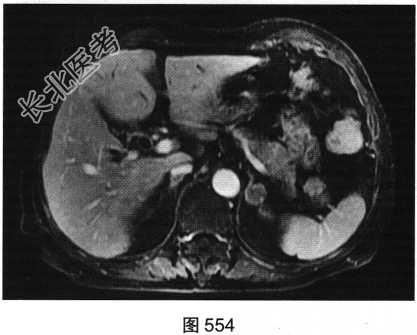

- 多项选择题3.[提示]MRI平扫+增强(图550~图555):T1WI正相位, 左侧肾上腺外侧肢可见类圆形T1WI稍高信号结节。T1WI反相位,结节信号明显减低。T2WI脂肪抑制, 结节呈均匀低信号。动态增强,动脉期结节轻度均匀强化, 静脉期结节呈相对低信号,延迟期结节呈相对低信号。可考虑的鉴别诊断为( )